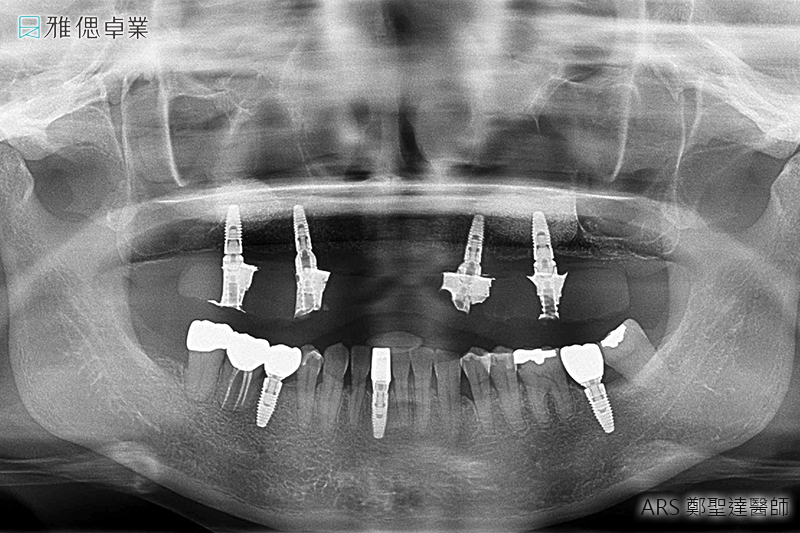

STEP1 諮詢、醫師診斷、收集相關資料與規劃療程

在醫師了解您的需求後,會拍攝斷層掃描、取得齒顎模型,製作數位手術導引板,擬定治療計畫,同時醫師會利用植牙模擬軟體,精準判斷植牙位置,提升植牙的成功率,讓植牙更精準、更安全。

STEP2 植入人工植牙手術

局部麻醉後,醫師會利用手術導引板抓取精準位置與角度,將植體放入齒槽骨中,先進的數位導引板不僅能縮小手術誤差,同時也可控制傷口範圍,使植牙術後的癒合更為迅速。植入人工牙根後,骨細胞就開始進行植體的整合。

- X光檢查:在第1,3,5,7,10,15年回診時檢查骨質密度、骨頭高度的變化及牙根與支台齒的密合度。